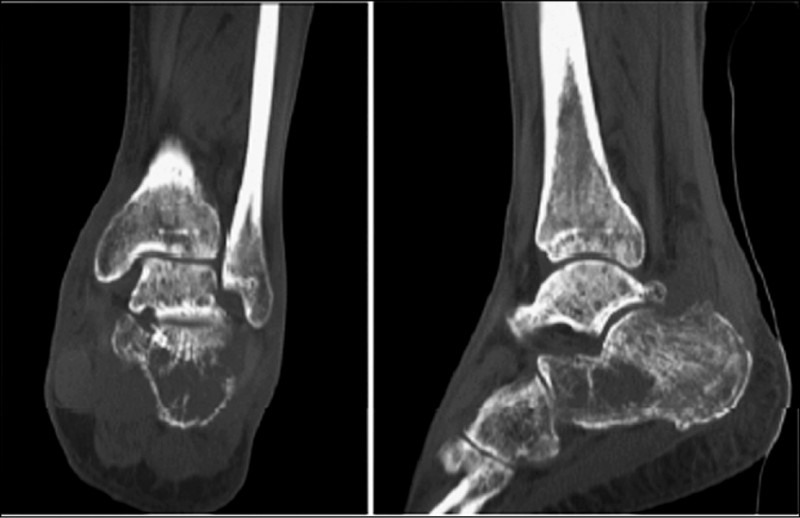

為釐清病因,醫療團隊進一步安排核磁共振檢查(MRI),MRI顯示足跟處存在1個腫瘤樣病灶,且周邊骨骼已有侵蝕情形,後續透過手術及病理切片,確認為「多發性骨髓瘤」。

經查詢國際醫學文獻,孤立發生於跟骨的多發性骨髓瘤極為罕見,全球迄今僅有4例相關報告,本案例為極具醫學價值的第5例。